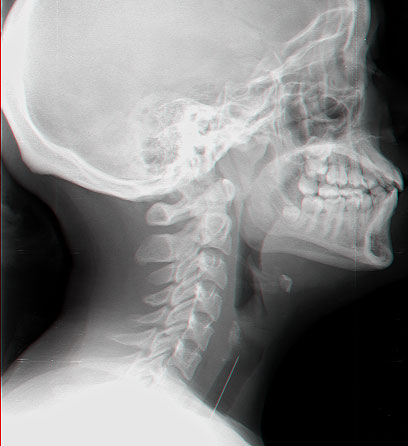

הסיכה בצילום הרנטגן, לפני שעשתה דרכה לקיבה

במקום לקניות, מייד לקחו הוריה של מראם את בתם לבית החולים "העמק" בעפולה. בצילום רנטגן נצפתה סיכת הראש בחלק העליון של כלי הנשימה, אולם כשנלקחה לחדר הניתוח הסיכה כבר לא היתה שם. צילום נוסף העלה כי הסיכה הגיעה בינתיים לקיבה.

"אנחנו משערים שבסיפור הזה קרה מקרה נדיר בו הנערה שאפה את הסיכה והיא נתקעה בחלק העליון של קנה הנשימה, מתחת למיתרי הקול ושם גם מצאנו אותה בצילום רנטגן, אולם כנראה שלאחר מכן, עד שהוכנסה לחדר הניתוח, תוך כדי שיעול נפלטה הסיכה מן הקנה ונבלעה בוושט ומשם הגיעה לקיבה", מספר ד"ר דרור אשכנזי ממחלקת אף אוזן גרון בבית חולים העמק.